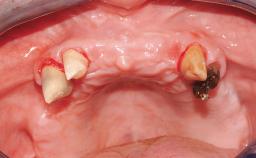

A 68-year-old, completely edentulous male patient presented for evaluation and treatment options. He reported excellent general health and was taking no regular medication. He had been edentulous for approximately 12 years, having lost his teeth to periodontal disease and dental caries. The patient’s chief complaint was incompetent function. His secondary concerns included his appearance and the desire for a predictable outcome. He attributed his reduced functional capacity to his lower complete denture, which he described as poor. He was particularly concerned with the denture’s instability and poor fit. In general terms, he was satisfied with the maxillary complete prosthesis. The maxillary prosthesis was characterized by adequate retention, stability, and support, although the fit was considered less than ideal.

Case Type Edentulous Mandible

Jaw Mandible

Area Full-Arch